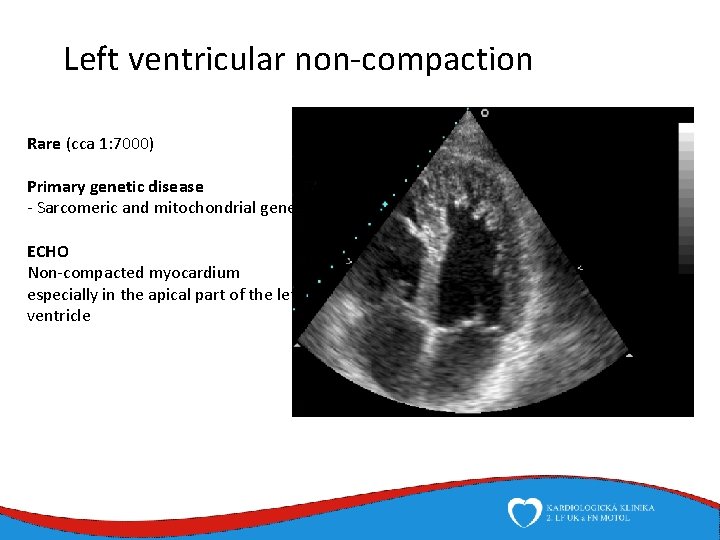

Left ventricular non-compaction Rare (cca 1: 7000) Primary genetic disease - Sarcomeric and mitochondrial genes ECHO Non-compacted myocardium especially in the apical part of the left ventricle